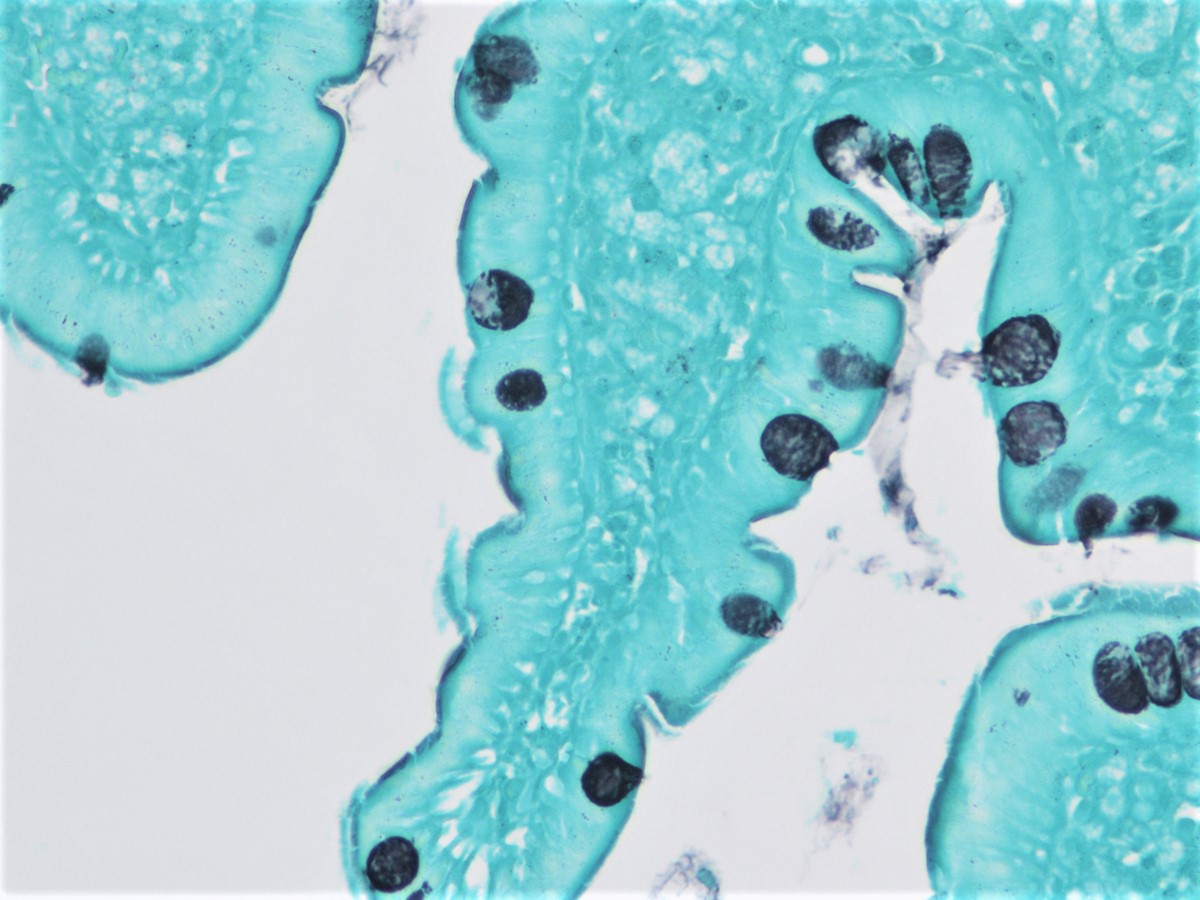

Фотографии медицинских исследований инсулиномы и синдрома Триады Уиппла